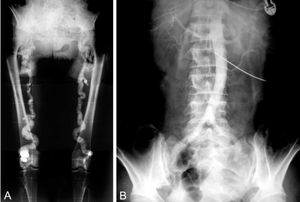

- 묀케베르그 경화증(Mönckeberg medial sclerosis): 주로 50세 이상의 노인에서 근육형 동맥에 칼슘이 침착되는 현상이다. 혈관 내강이 좁아지는 정도가 미미하며 임상적으로 큰 의미는 없다.

- 묀케베르그 경화증(Mönckeberg medial sclerosis)은 주로 50세 이상의 노인에서 근육형 동맥에 칼슘이 침착되는 현상이다. 혈관 내강이 좁아지는 정도가 미미하며 임상적으로 큰 의미는 없다.

동맥 중막에 칼슘이 축적되어 석회화됨으로써 진행되는 동맥경화증도 있다. 이 경우 혈관 내부의 협착은 관찰되지 않지만,[21] 중막이 단단하고 부서지기 쉬워져 혈관(혈관벽) 파열로 이어질 수 있다.[26][27] 주로 대동맥이나 하지의 동맥, 경부의 동맥에서 잘 발생하며, 50세 이상의 남녀에게 많이 나타난다.[21]